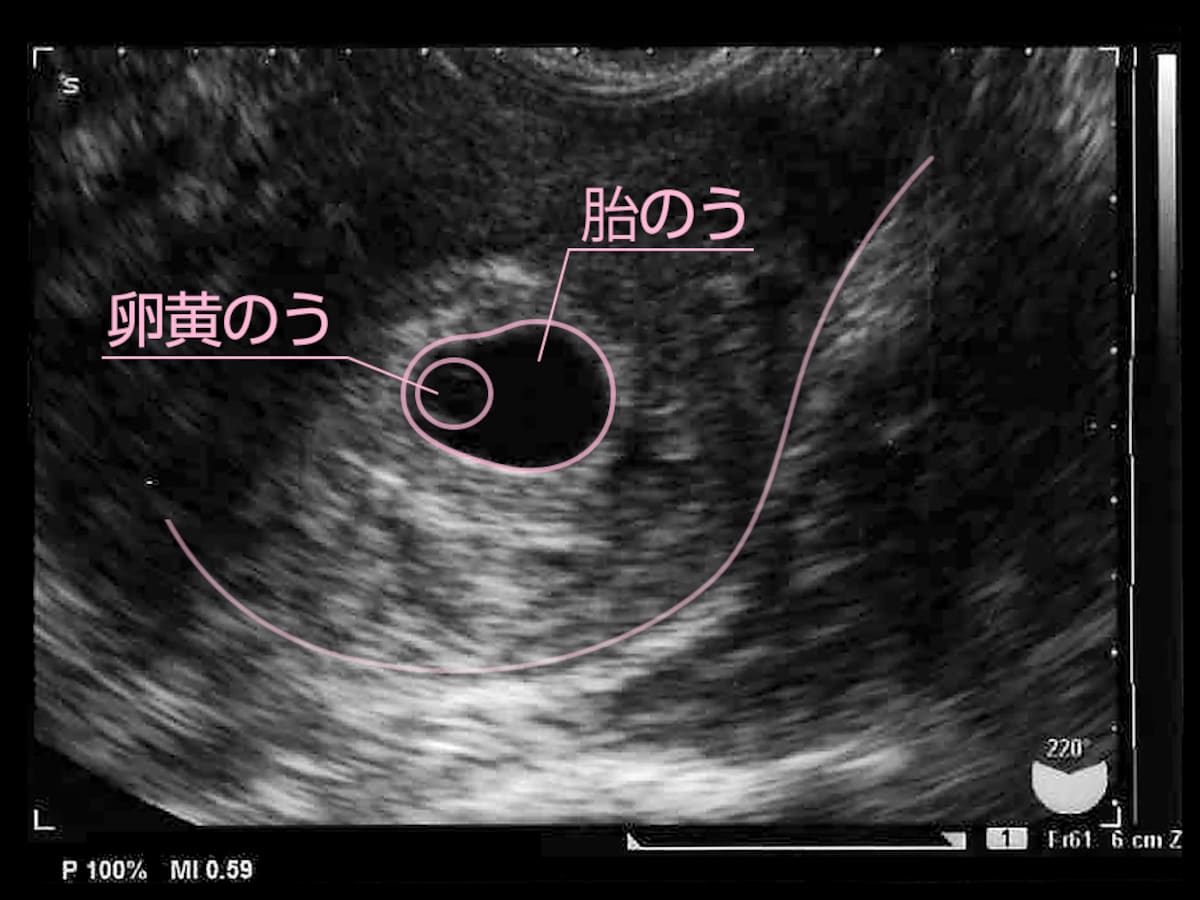

医療監修 胎嚢 たいのう とは 確認方法や確認できる時期を知ろう ママリ

初めてパパ用 胎嚢 たいのう 超音波エコー検査の見方 6週0日 プレパパ獣医 子供と猫とrichになるブログ

この胎嚢の中に卵黄嚢 うっすら見えますか この胎嚢の中に卵黄嚢 妊娠 教えて Goo

卵黄嚢が見えた でも胎嚢は小さい 助産師さきの不妊治療で年子 0才 2才 育児